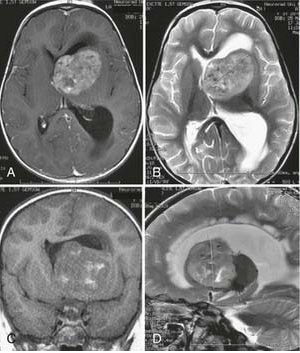

3歲女孩Nina活潑可愛,一直是全家人的小寶貝。然而在幼兒園正在玩耍的她,突然暈倒,被老師送到醫(yī)院時(shí),父母害怕較了。經(jīng)過全身檢查,發(fā)現(xiàn)孩子側(cè)腦室里長(zhǎng)了個(gè)瘤子(圖A、B、C、D)。醒來之后,孩子變得糊糊涂涂,父母也分不清、意識(shí)障礙。較初為了緩解孩子的癥狀,放置外部腦室引流管來治療閉塞性腦積水。分流手術(shù)后,孩子癥狀慢慢緩解,意識(shí)也開始慢慢清醒。然而,孩子的腫瘤太大了,需采取外科手術(shù)將其切除。

這么小的孩子,這么大的腫瘤,誰來為孩子手術(shù)呢?一個(gè)病友了下德國(guó)INI國(guó)際神經(jīng)學(xué)研究所的神經(jīng)外科教授巴特朗菲(Helmut Bertalanffy)教授。巴特朗菲教授愿意為他手術(shù)。在術(shù)中神經(jīng)導(dǎo)航(圖E)的幫助下,Nina在仰臥位接受了手術(shù)。

術(shù)后磁共振成像顯示間變性室管膜瘤被完全切除(F-H)。術(shù)后過程順利,無新發(fā)神經(jīng)功能缺損,患兒接受了化療。